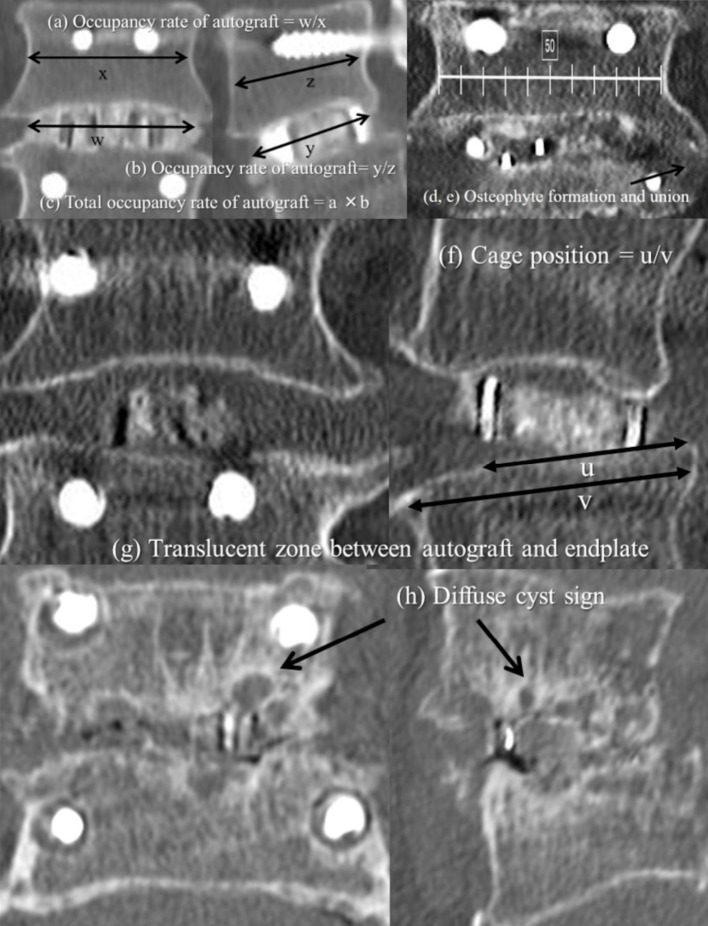

Methods: A total of 138 patients (mean age, 67 years; follow-up period, 12 months) who underwent single-level PLIF or TLIF were retrospectively analyzed. CS was defined as >1 mm sinking of the intervertebral cage evaluated via computed tomography. The patients were divided into the CS and nonsubsidence (NS) groups. HRQOL was assessed using the Oswestry Disability Index (ODI) scores.

Results: Among the 138 patients, 30 (22%) developed CS following PLIF or TLIF. All cases with TLIF surgery (n=25) involved the use of one cage. A significant difference was observed in the use of two cages between the CS and NS groups (20.0% vs. 48.1%; P=0.006). The CS group had lower occupancy rate of autograft soon after the operation than the NS groups (P=0.002), and the occupancy rate of autograft tended to decrease in the CS group compared with the NS group over time. The ODI scores improved in both groups postoperatively; however, the NS group exhibited greater improvements in ODI scores from 4 months postoperatively. The CS group had a significantly lower proportion of patients with intervertebral osseous union at 6 and 12 months postoperatively compared with the NS group (P=0.003 and P<0.001, respectively).

Conclusions: The use of two intervertebral cages may enhance initial stability and reduce CS risk after PLIF. Initial intervertebral stability was crucial to preventing CS occurrence, as evidenced by the high occupancy rates of autograft in patients without CS. Surgical factors, including surgical strategy and intraoperative techniques, should be considered to prevent CS occurrence and to improve surgical outcomes and patient satisfaction.